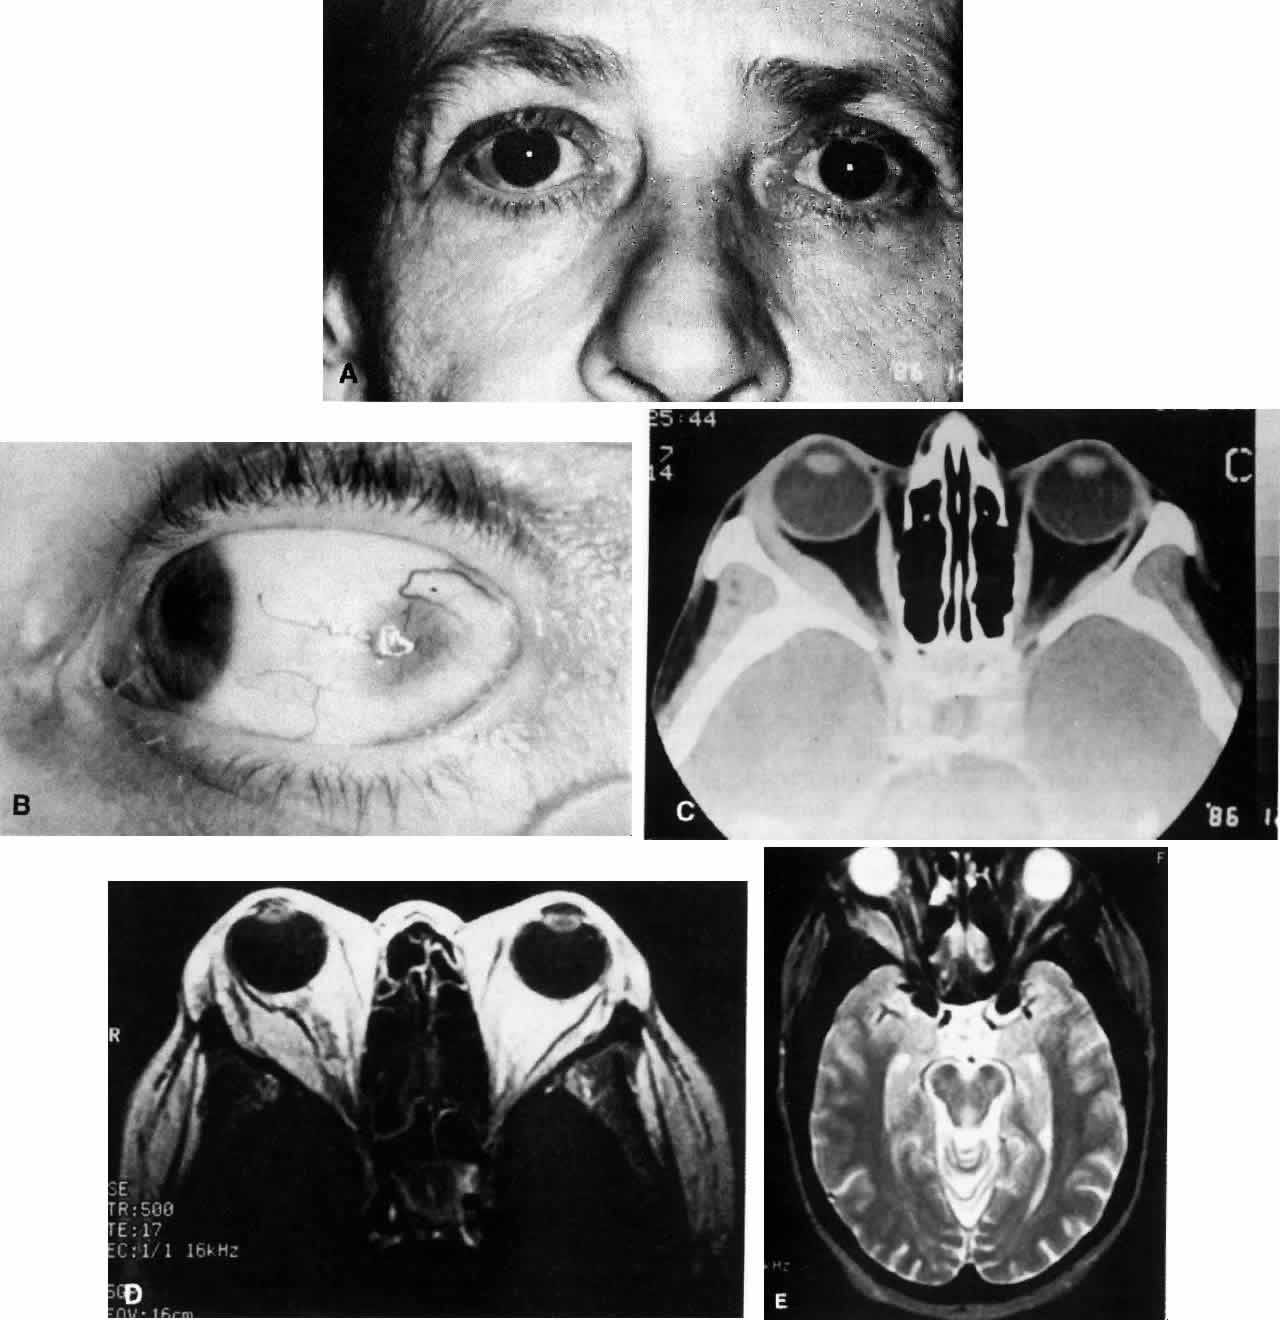

Fig. 1. A. A 36-year-old woman presented with right-sided pain and proptosis occurring over a several-day period. Externally the eye is quiet and does not appear inflamed. The patient had no complaints of diplopia or other visual disturbances. Tissue obtained at biopsy demonstrated idiopathic orbital inflammation. B. Axial CT image from the same patient demonstrates bilateral orbital masses located laterally in the orbits. Note that masses are ill defined and do not appear to have a capsule. The masses are molded to the bony orbital walls without evidence of any bony irregularities. C. Coronal CT image from the patient again shows the presence of bilateral orbital masses apparently involving the lateral rectus muscles.

Fig. 2. A 54-year-old woman presented with acute orbital inflammation demonstrating significant proptosis and inflammatory signs involving the right orbit. In addition to severe pain, the patient had diplopia secondary to orbital edema and inflammation.

Fig. 3. A. A 62-year-old woman presented with diplopia and minimal right-sided proptosis. B. Enlarged lateral rectus muscle is visible subconjunctivally. C. Axial CT image confirms myositis involving the lateral rectus muscle. Note that the muscle as well as its tendon are involved in the inflammatory process in contrast to muscle involvement in thyroid-related orbital disease. D. T1-weighted MRI image demonstrating myositis involving the lateral rectus muscle. In this case the muscle belly is enlarged but the tendon appears relatively unaffected. E. T2 weighted MRI image of orbital myositis showing little difference in appearance of muscle between T1- and T2-weighted images.

Fig. 4. A and B. Gross specimen of old, burned out, involuted granuloma from a patient with idiopathic orbital inflammation. Note lack of vascularity.